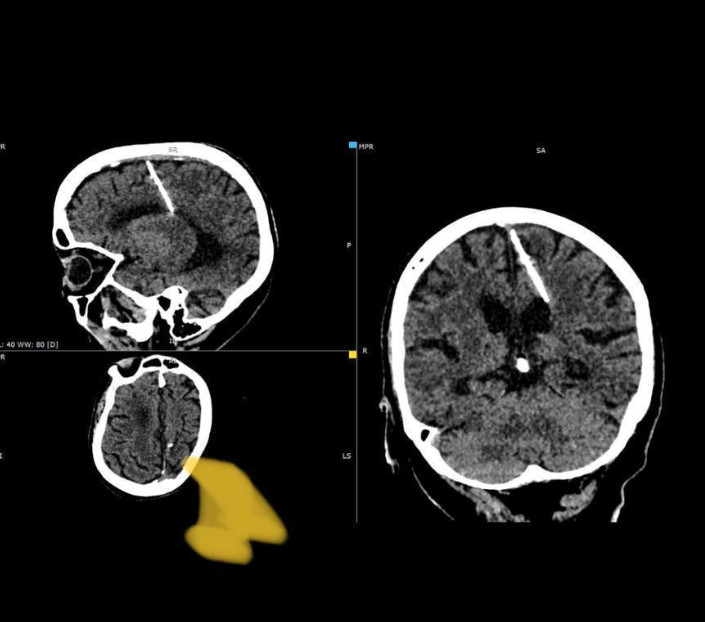

Κόσμος Ρωσία: Βρήκαν βελόνα στον εγκέφαλο 80χρονης – Απόδειξη ότι οι γονείς της αποπειράθηκαν να την σκοτώσουνΔεν παραπονέθηκε ποτέ για πονοκεφάλους 06/10/2023 09:52